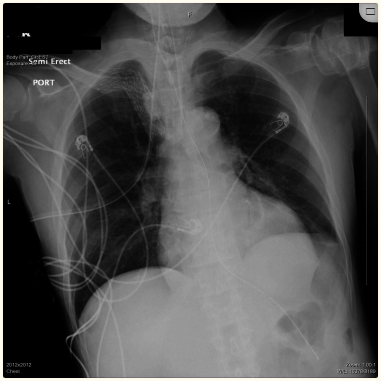

在控制血压的同时进行紧急血液透析。患者经经验静脉注射头孢曲松治疗5天,基于CXR进行浸润,每日进行HD治疗3天,其血容量和电解质有所改善。最初,他的呼吸状况随着需氧量的减少而改善,重复CXR显示肺水肿消失(图2)。头孢曲松治疗后,通过BAL收集的痰培养结果为阴性。然而,尽管排除了中枢脑病因并改善了代谢异常,但由于患者精神状态不佳,无法对其拔管。

图2、CXR显示肺水肿消失